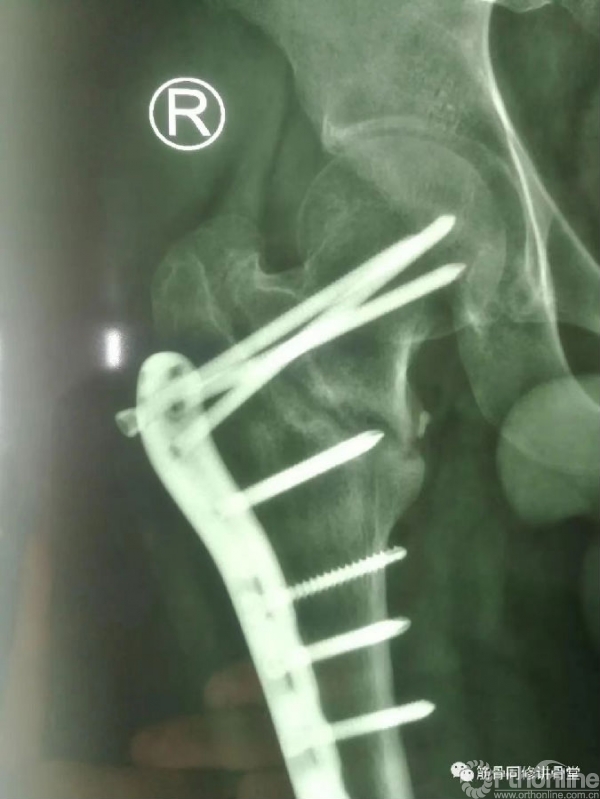

术后影像资料(2021.9.21)

骨折术后骨不连(2022.3)

骨折术后骨不连(2022.7.3)

手术过程:

(1)髂骨自体取骨,取适量松质骨;

(2)取出锁定钢板上的第4颗螺钉;

(3)DAA入路,切开关节囊;

(4)彻底刮除骨折断端纤维瘢痕组织;

(5)植入自体松质骨+BMP-2改善局部生物学环境;

(6)植入1/3管形板支撑,改善骨折愈合的生物力学环境。